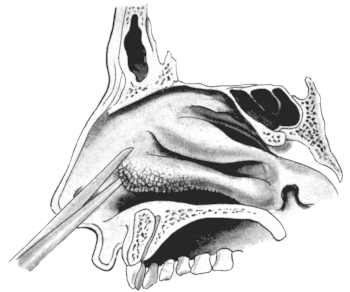

| 320. | Catheterizing the Maxillary Sinus | 626 |

| 333. | Catheterizing the Frontal Sinus | 639 |